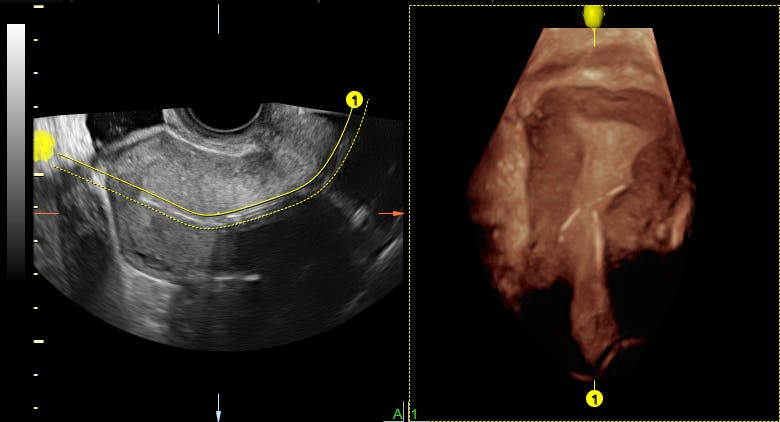

In case of one patient she tried to do nuchal translucency ultrasound with transabdominal approach but due to maternal body habitus and fetal position she also used transvaginal. It should not be confused with the nuchal fold, which is seen in the second trimester. It is same as normal sound in its physical properties, but humans cannot hear it. When the nt is greater than 3.5 mm, there is a 1 in 5 chance of a chromosome abnormality such as turner or down syndrome, or trisomy 18. Nt focuses on a small, clear space at the back of a growing baby's neck called the nuchal fold. This means that you get to watch your child move within the womb. The nuchal translucency scan (also called the nt scan) uses ultrasound to assess your developing baby's risk of having down syndrome (ds) and some other chromosomal abnormalities, as well as major congenital heart problems. Increased fluid could indicate a risk of abnormality (such as down syndrome or other genetic disorder or birth defect) to the baby.

Additional tests should be ordered by an ob or genetic counselor for confirmation. Normally she does it with transabdominal approach. Nuchal translucency (nt) measurement nuchal translucensy (nt) is the clear space in the tissue of your developing baby's neck. This test measures the size of the clear tissue, called the nuchal translucency, at the back of your. At times, the nuchal translucency test may add on ultrasound markers, such as measuring a baby's. What do ultrasound abbreviations and initials mean? On my nt ultrasound says har high what does it mean. The letters that are next to the numbers on an ultrasound represent different measurements of the baby. Nuchal translucency ultrasound alone can also provide this risk assessment, but it is not as accurate as combined first trimester screening. Among the many terms you will learn and become familiar with is a nuchal scan. It is same as normal sound in its physical properties, but humans cannot hear it. Most babies with a large nt will be healthy at birth. The nuchal translucency scan (also called the nt scan) uses ultrasound to assess your developing baby's risk of having down syndrome (ds) and some other chromosomal abnormalities, as well as major congenital heart problems.

During the ultrasound examination, a thin layer of fl uid at the back of the neck called the nuchal translucency (nt) is measured. A nuchal translucency screening, or nt screening, is a specialized routine ultrasound performed at the end of the first trimester of pregnancy. It helps doctors determine if a baby is statistically more likely to have a chromosomal abnormality. The nuchal translucency screening, or nt, is a prenatal ultrasound test that can help to determine the fetus's likelihood of having down syndrome or some other chromosome abnormality. What does nt mean on an ultrasound :

Ultrasound measurement and a blood test. Major heart problems can also be detected using the nt prenatal test. Normally she does it with transabdominal approach. The first stage involves an ultrasound examination to precisely determine the gestational age of the pregnancy and to measure the nuchal translucency (nt) thickness, a space at the back of the baby's neck; An nt measurement can help your healthcare practitioner assess your baby's risk of having down syndrome and some other chromosomal abnormalities as well as major congenital heart problems. A special ultrasound, called a nuchal translucency screening, measures the back of the baby's neck. It helps doctors determine if a baby is statistically more likely to have a chromosomal abnormality. The nt is considered large when it is 3.0 mm (about 1/8 inch) or more.

Meaning of ultrasound in english. The ultrasound nt scan or nuchal translucency scan is an ultrasound to measure the amount of fluid that has been collected in the back of the neck of the fetus. The first stage involves an ultrasound examination to precisely determine the gestational age of the pregnancy and to measure the nuchal translucency (nt) thickness, a space at the back of the baby's neck; An ultrasound is an imaging test that uses sound waves to create pictures of structures inside the body. A nuchal translucency screening, or nt screening, is a specialized routine ultrasound performed at the end of the first trimester of pregnancy. This test measures the size of the clear tissue, called the nuchal translucency, at the back of your. The fourth dimension is time, because it is a video and not just a still image. This is the ultrasound typically completed at the 12 week mark of pregnancy. First trimester screening includes an ultrasound exam to measure the size of the clear space in the tissue at the back of a baby's neck (nuchal translucency). However, a large nt size means a higher. Major heart problems can also be detected using the nt prenatal test. A 4d ultrasound creates a live motion video. Nuchal translucency (nt) ultrasound is a diagnostic prenatal screening assessment prescribed to detect chromosomal abnormalities associated with down syndrome (trisomy 21), one of the most common genetic conditions affecting 1 in 700 u.s.